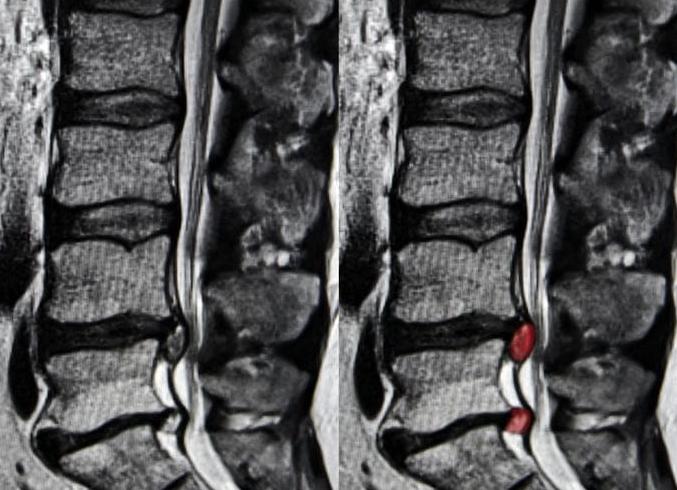

При диагностическом сканировании на МРТ грыжа позвоночника на снимках выглядит как выпячивание объемного образования (иногда достигающее 2 см в размерах) в межпозвонковое пространство, сужающее позвоночный спинномозговой канал. Проведение МРТ грыжи показано при любых болях причиной которых является сдавливание нервных окончаний в межпозвоночном пространстве.

МРТ поясничного отдела позвоночника. Сагиттальная Т2-взвешенная МРТ. Грыжа диска.

МРТ поясничного отдела позвоночника. Сагиттальная Т2-взвешенная МРТ. Секвестрировавшаяся грыжа диска.